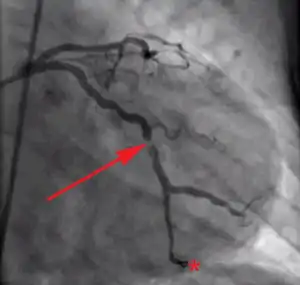

![]() Acute coronary syndromes are commonly caused by a blood clot forming on an atherosclerotic plaque in a coronary artery. Oxygen delivery to a part of heart muscle is blocked, eventually causing cell death. | |

Management of acute coronary syndrome is targeted against the effects of reduced blood flow to the affected area of the heart muscle, usually because of a blood clot in one of the coronary arteries, the vessels that supply oxygenated blood to the myocardium. This is achieved with urgent hospitalization and medical therapy, including drugs that relieve chest pain and reduce the size of the infarct, and drugs that inhibit clot formation; for a subset of patients invasive measures are also employed (coronary angiography and percutaneous coronary intervention). Basic principles of management are the same for all types of acute coronary syndrome. However, some important aspects of treatment depend on the presence or absence of elevation of the ST segment on the electrocardiogram, which classifies cases upon presentation to either ST segment elevation myocardial infarction (STEMI) or non-ST elevation acute coronary syndrome (NST-ACS); the latter includes unstable angina and non-ST elevation myocardial infarction (NSTEMI). Treatment is generally more aggressive for STEMI patients, and reperfusion therapy is more often reserved for them. Long-term therapy is necessary for prevention of recurrent events and complications.[1]